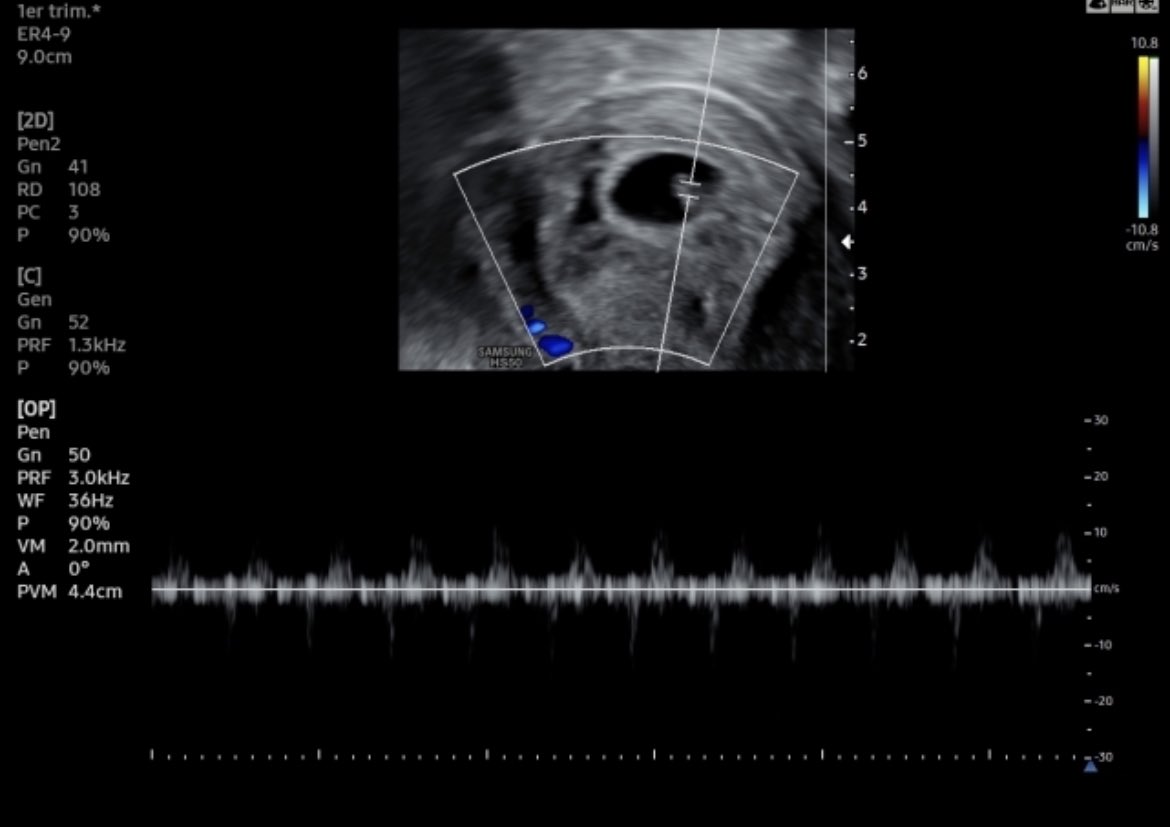

#infertilpandy hoy teníamos la eco de control. Hay embrión y hay latido. Es muy pequeñito aún, pero nos ha dicho que todo bien. Tenemos la eco oficial de RA el 06/06. Estamos muy felices, emocionados, contentos… en fin que os voy a contar #pasitoapasito 🎉🎊🍀🎉❤️💗🙏🏻

#infertilpandy hoy teníamos la eco de control. Hay embrión y hay latido.

Es muy pequeñito aún, pero nos ha dicho que todo bien. Tenemos la eco oficial de RA el 06/06. Estamos muy felices, emocionados, contentos… en fin que os voy a contar #pasitoapasito 🎉🎊🍀🎉❤️💗🙏🏻

#infertilpreñis chicas, hoy me atrevo a usar este #, hoy hemos tenido la eco ofícial de RA SS, estoy de 7+6 y hemos visto al embri que ahora mide 13mm y hemos escuchado su latido, nos ha dicho que todo marcha bien y nos han dado el alta. Estamos muy muy felices 😁❤️🤰🏽🎉

#infertilpreñis Hola chicas, ayer nos hicieron la eco de 1er trimestre y nos ha salido todo bien, riesgo bajo en todo. Esto parece un sueño, estoy muy agradecida con la vida pero siempre pensando en la pandy. Ojalá pronto ojalá todas. 🍀❤️🍀